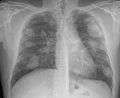

For uncomplicated silicosis, chest x-ray will confirm the presence of small (< 10 mm) nodules in the lungs, especially in the upper lung zones. Using the ILO classification system, these are of profusion 1/0 or greater and shape/size "p", "q", or "r". Lung zone involvement and profusion increases with disease progression. In advanced cases of silicosis, large opacity (> 1 cm) occurs from coalescence of small opacities, particularly in the upper lung zones. With retraction of the lung tissue, there is compensatory emphysema. Enlargement of the hilum is common with chronic and accelerated silicosis. In about 5-10% of cases, the nodes will calcify circumferentially, producing so-called "eggshell" calcification. This finding is not pathognomonic (diagnostic) of silicosis. In some cases, the pulmonary nodules may also become calcified.

Chest X-ray showing uncomplicated silicosis

Complicated silicosis

Silicosis ILO Classification 2-2 R-R